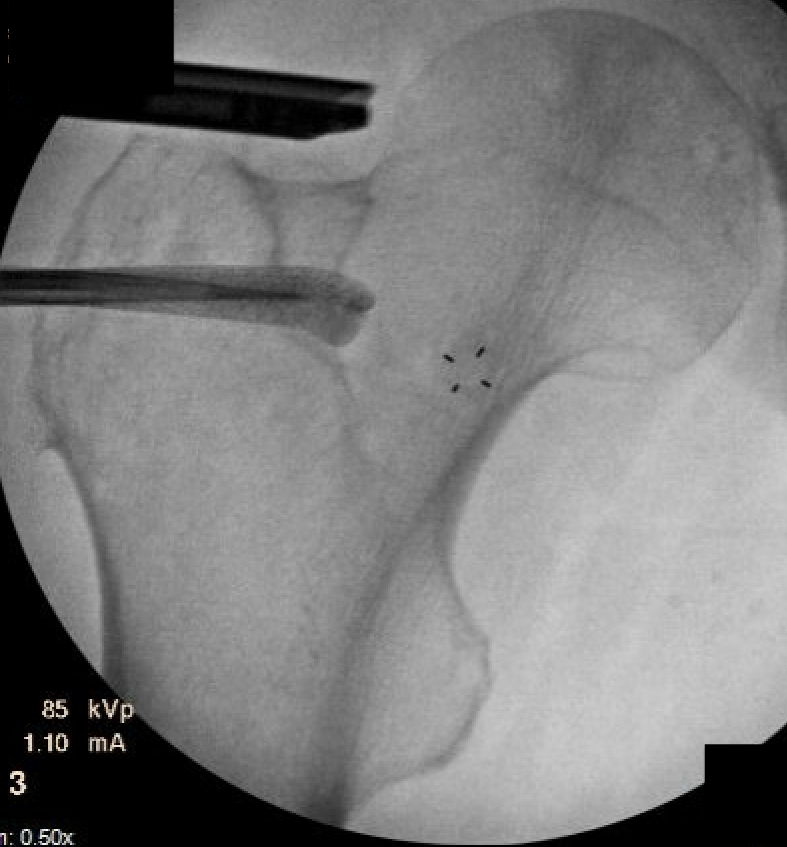

CT

IFI

IFIIFIIFI

Injections

CT / Ultrasound guided local anesthetic and cortisone around quadratus

- diagnostic

- +-/ therapeutic